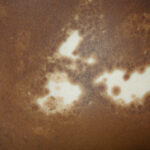

CLINICAL FINDINGS

Patients with vitiligo present with one to several amelanotic macules that appear chalk- or milk-white in color. The lesions are usually well-demarcated, but the margins may be scalloped. They are accentuated on Wood's lamp examination. Lesions enlarge centrifugally at an unpredictable rate and can appear on any body site, including mucous membranes. However, initial lesions occur most frequently on the hands, forearms, feet, and face. When vitiligo occurs on the face, it often favors a perioral and periocular distribution.

Depending on ethnic color, vitiligo is more or less conspicuous .